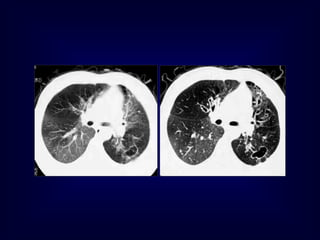

Lymphangioleiomyomatosis

(LAM)

HRCT Morphology

Thin-walled cysts (2mm - 5cm)

Uniform in size / rarely confluent

Homogeneous distribution

Chylous pleural effusion

Lymphadenopathy

in young women

Tuberous Sclerosis (young man)